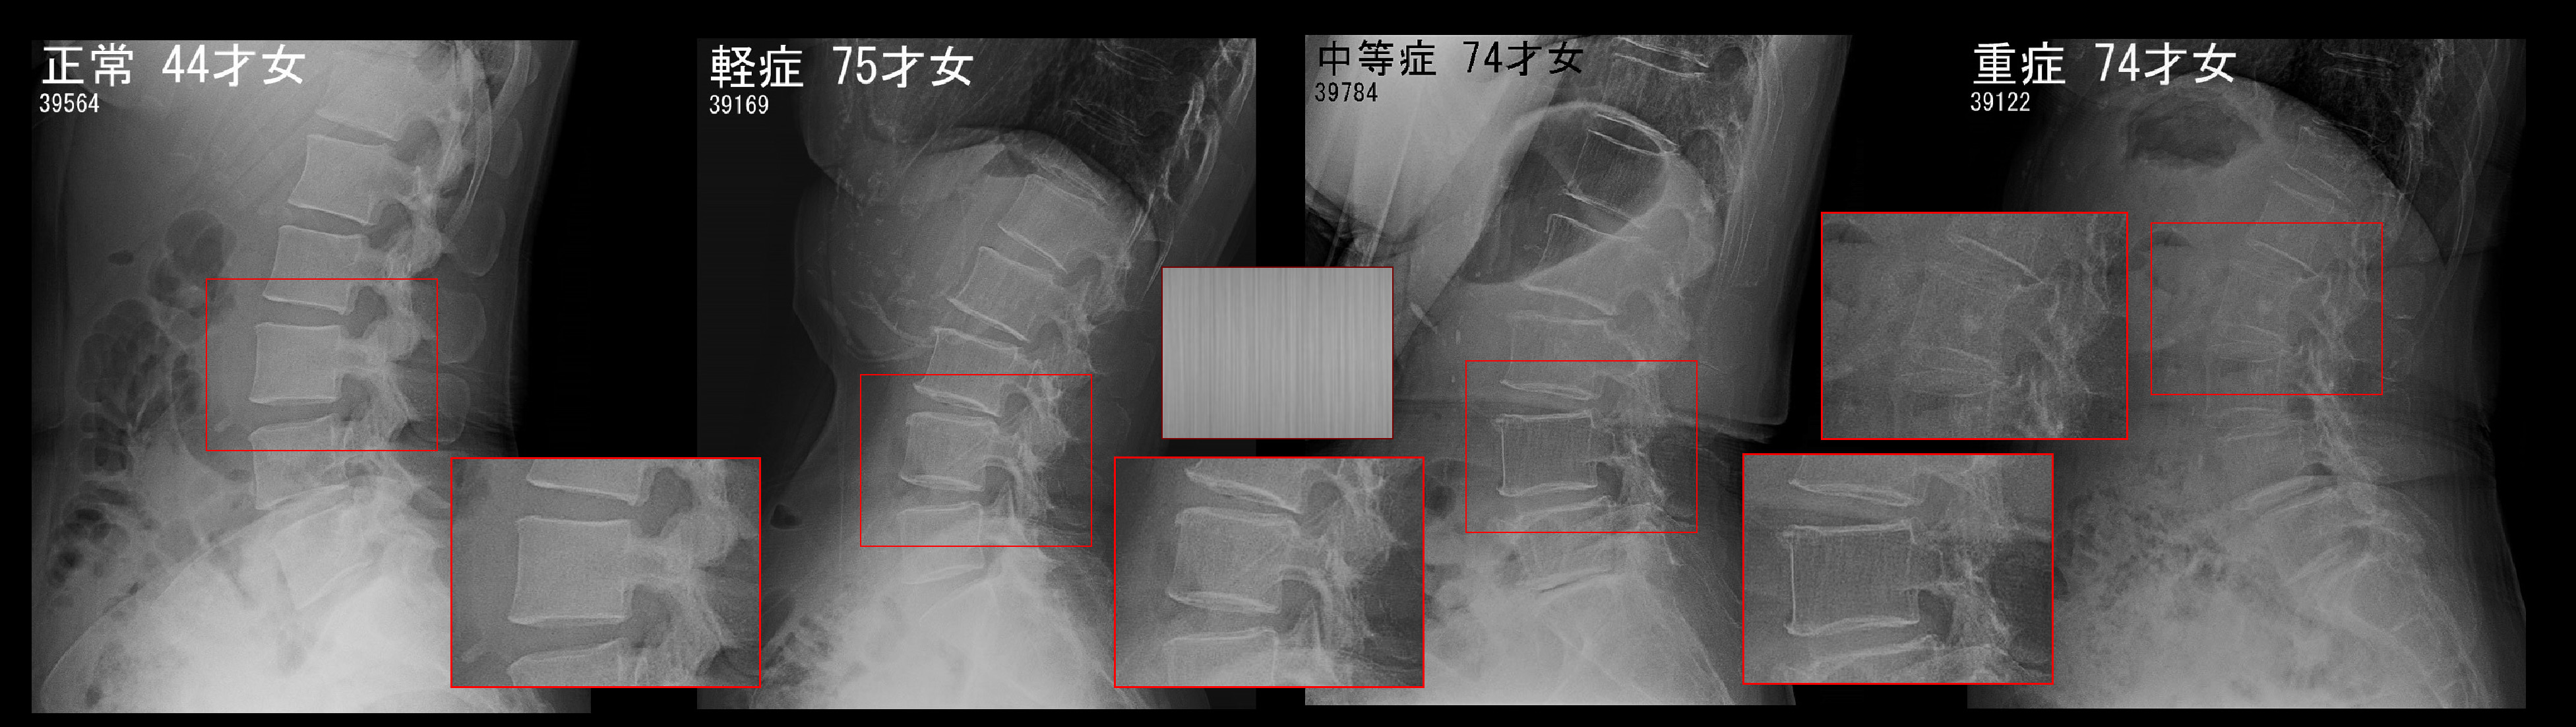

骨粗鬆症の腰椎(腰骨)レントゲン像と骨量測定の検査方法について説明します。

骨粗鬆症Xpb.jpg上図が腰椎レントゲン像での骨粗鬆症の診断となります。正常は正方形のような腰骨は均一に白くなっています。これが骨粗鬆症の軽症となると腰骨の模様は砂をほうきで掃いたような縦線の模様(またはつや消しのステンレスの模様)となってきます。骨粗鬆症が中等度となると縦線の模様の縦線1本1本が確認可能な印象となります。骨粗鬆症が重度となると、縦線の模様は確認困難となります。中等度までの骨粗鬆症では腰骨の輪郭ははっきりと認識可能ですが、重度では四角形の輪郭(特に前方の縦の線)の認識が困難となります。このレントゲン像での診断は定性的診断法ですが、骨粗鬆症の治療においては定量的診断が不可欠となります。